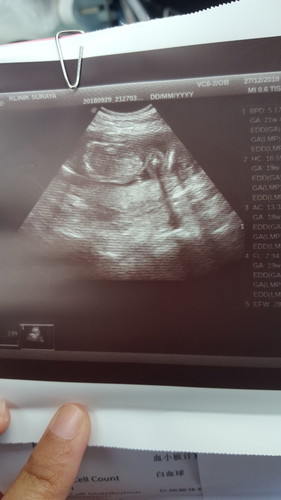

Semalam scan untuk 18 minggu. Doktor cakap uri di bawah dan sekarang saya rasa cramp sangat bawah perut. Nak buat apa pun tak boleh. Ada sesiapa ada tips untuk kurang kan rasa cramp tu? Nak urut takut

Uri kat bawah tak boleh urut sis.. Byk kan berehat je.. Kalau kat dalam wad pun mmg doc suruh baring je..